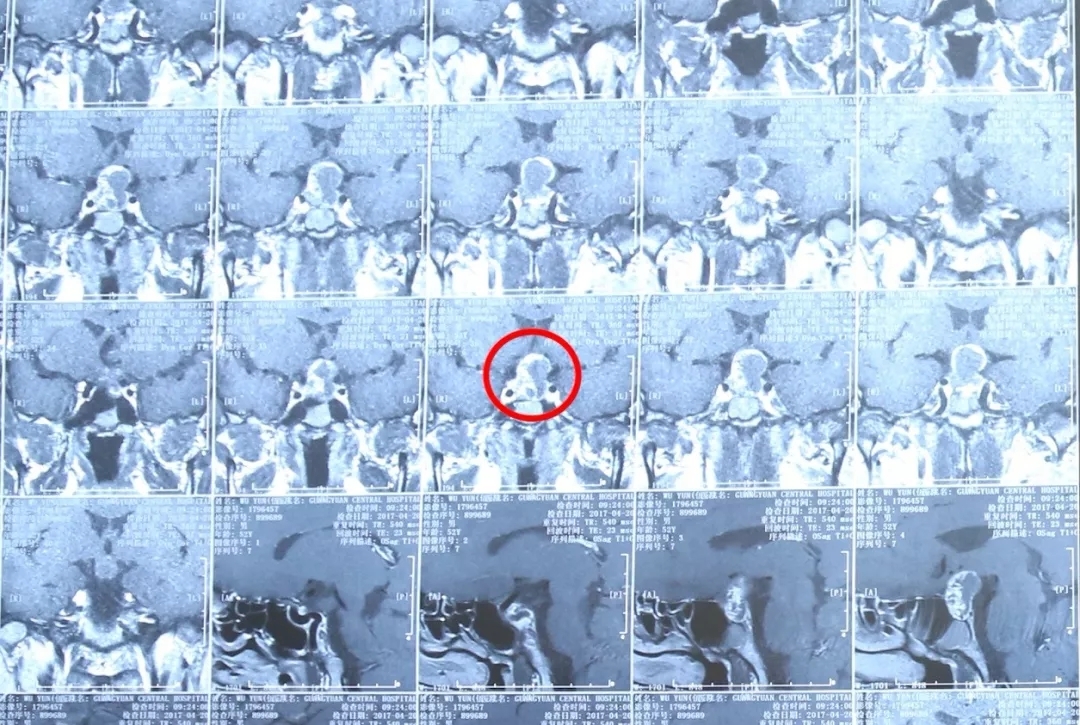

04 颅咽管瘤

颅咽管瘤为先天性肿瘤,约占颅内肿瘤的5%。多见于儿童及少年,男性多于女性。临床常表现为颅内压增高、双侧视力减退、视野缺损、精神不振、嗜睡、记忆力减退、反应迟钝、思维混乱、多饮多尿等。

颅咽管瘤患者MRI